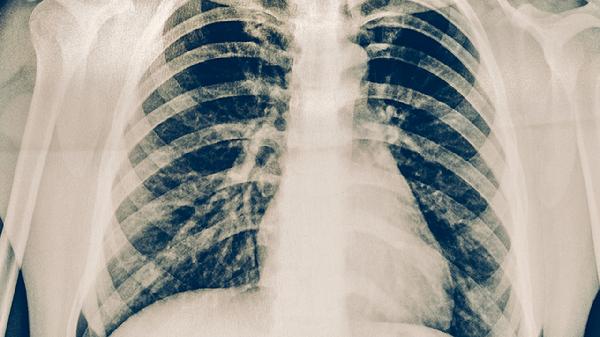

肺結(jié)核的局部癥狀主要有咳嗽、咳痰、咯血、胸痛、呼吸困難等。肺結(jié)核是由結(jié)核分枝桿菌感染引起的慢性傳染病,主要累及肺部,但也可侵犯其他器官。

約三分之一的肺結(jié)核患者會(huì)出現(xiàn)咯血癥狀,表現(xiàn)為痰中帶血或大量咯血??┭饕捎诜尾坎≡钋治g血管所致,嚴(yán)重時(shí)可危及生命。少量咯血時(shí)可使用云南白藥膠囊等止血藥物,大量咯血需立即就醫(yī)。抗結(jié)核治療同時(shí)可配合使用氨基己酸注射液等止血?jiǎng)?/p>

肺結(jié)核晚期或病變范圍廣泛時(shí)可出現(xiàn)呼吸困難,表現(xiàn)為氣促、喘息等。呼吸困難與肺組織破壞、胸腔積液等因素有關(guān)。患者應(yīng)保持半臥位,必要時(shí)吸氧。除規(guī)范抗結(jié)核治療外,可配合使用氨茶堿片等平喘藥物。